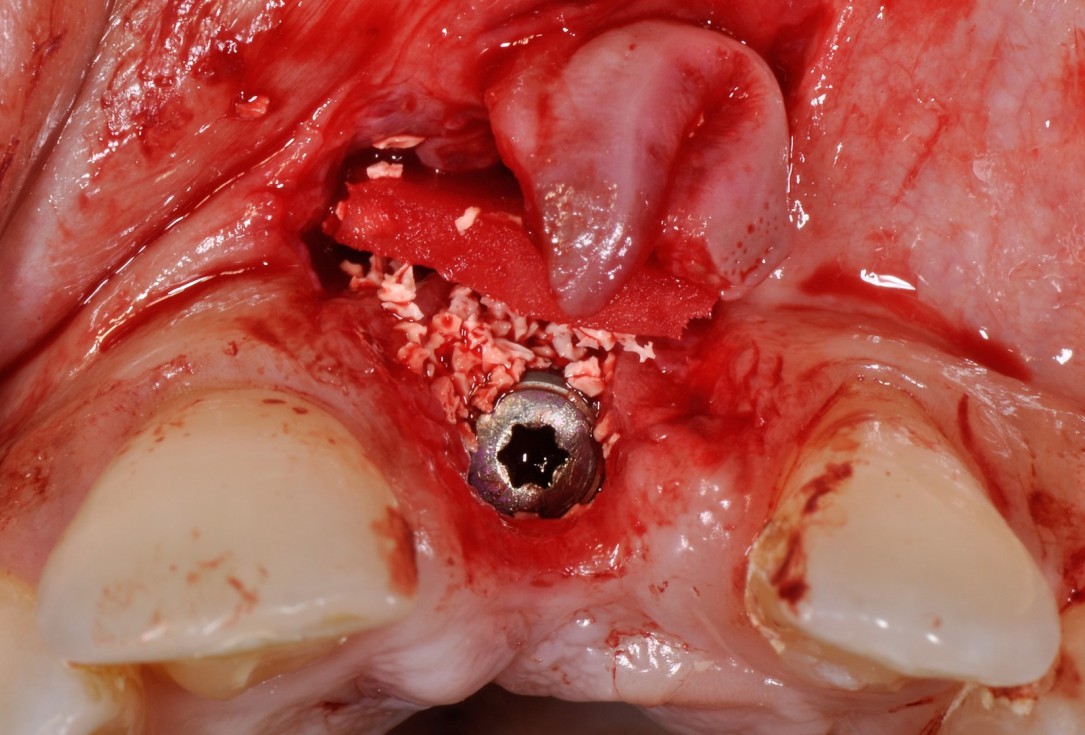

Immediate implant placement with cerabone® and mucoderm® - Dr. F. Rossi - Vestibular wall defect visible after extraction of tooth 11Immediate implant placement with cerabone® and mucoderm® - Dr. F. Rossi

Immediate implant placement with cerabone® and mucoderm® - Dr. F. Rossi - Implant placement and augmentation with cerabone® and mucoderm®Immediate implant placement with cerabone® and mucoderm® - Dr. F. Rossi